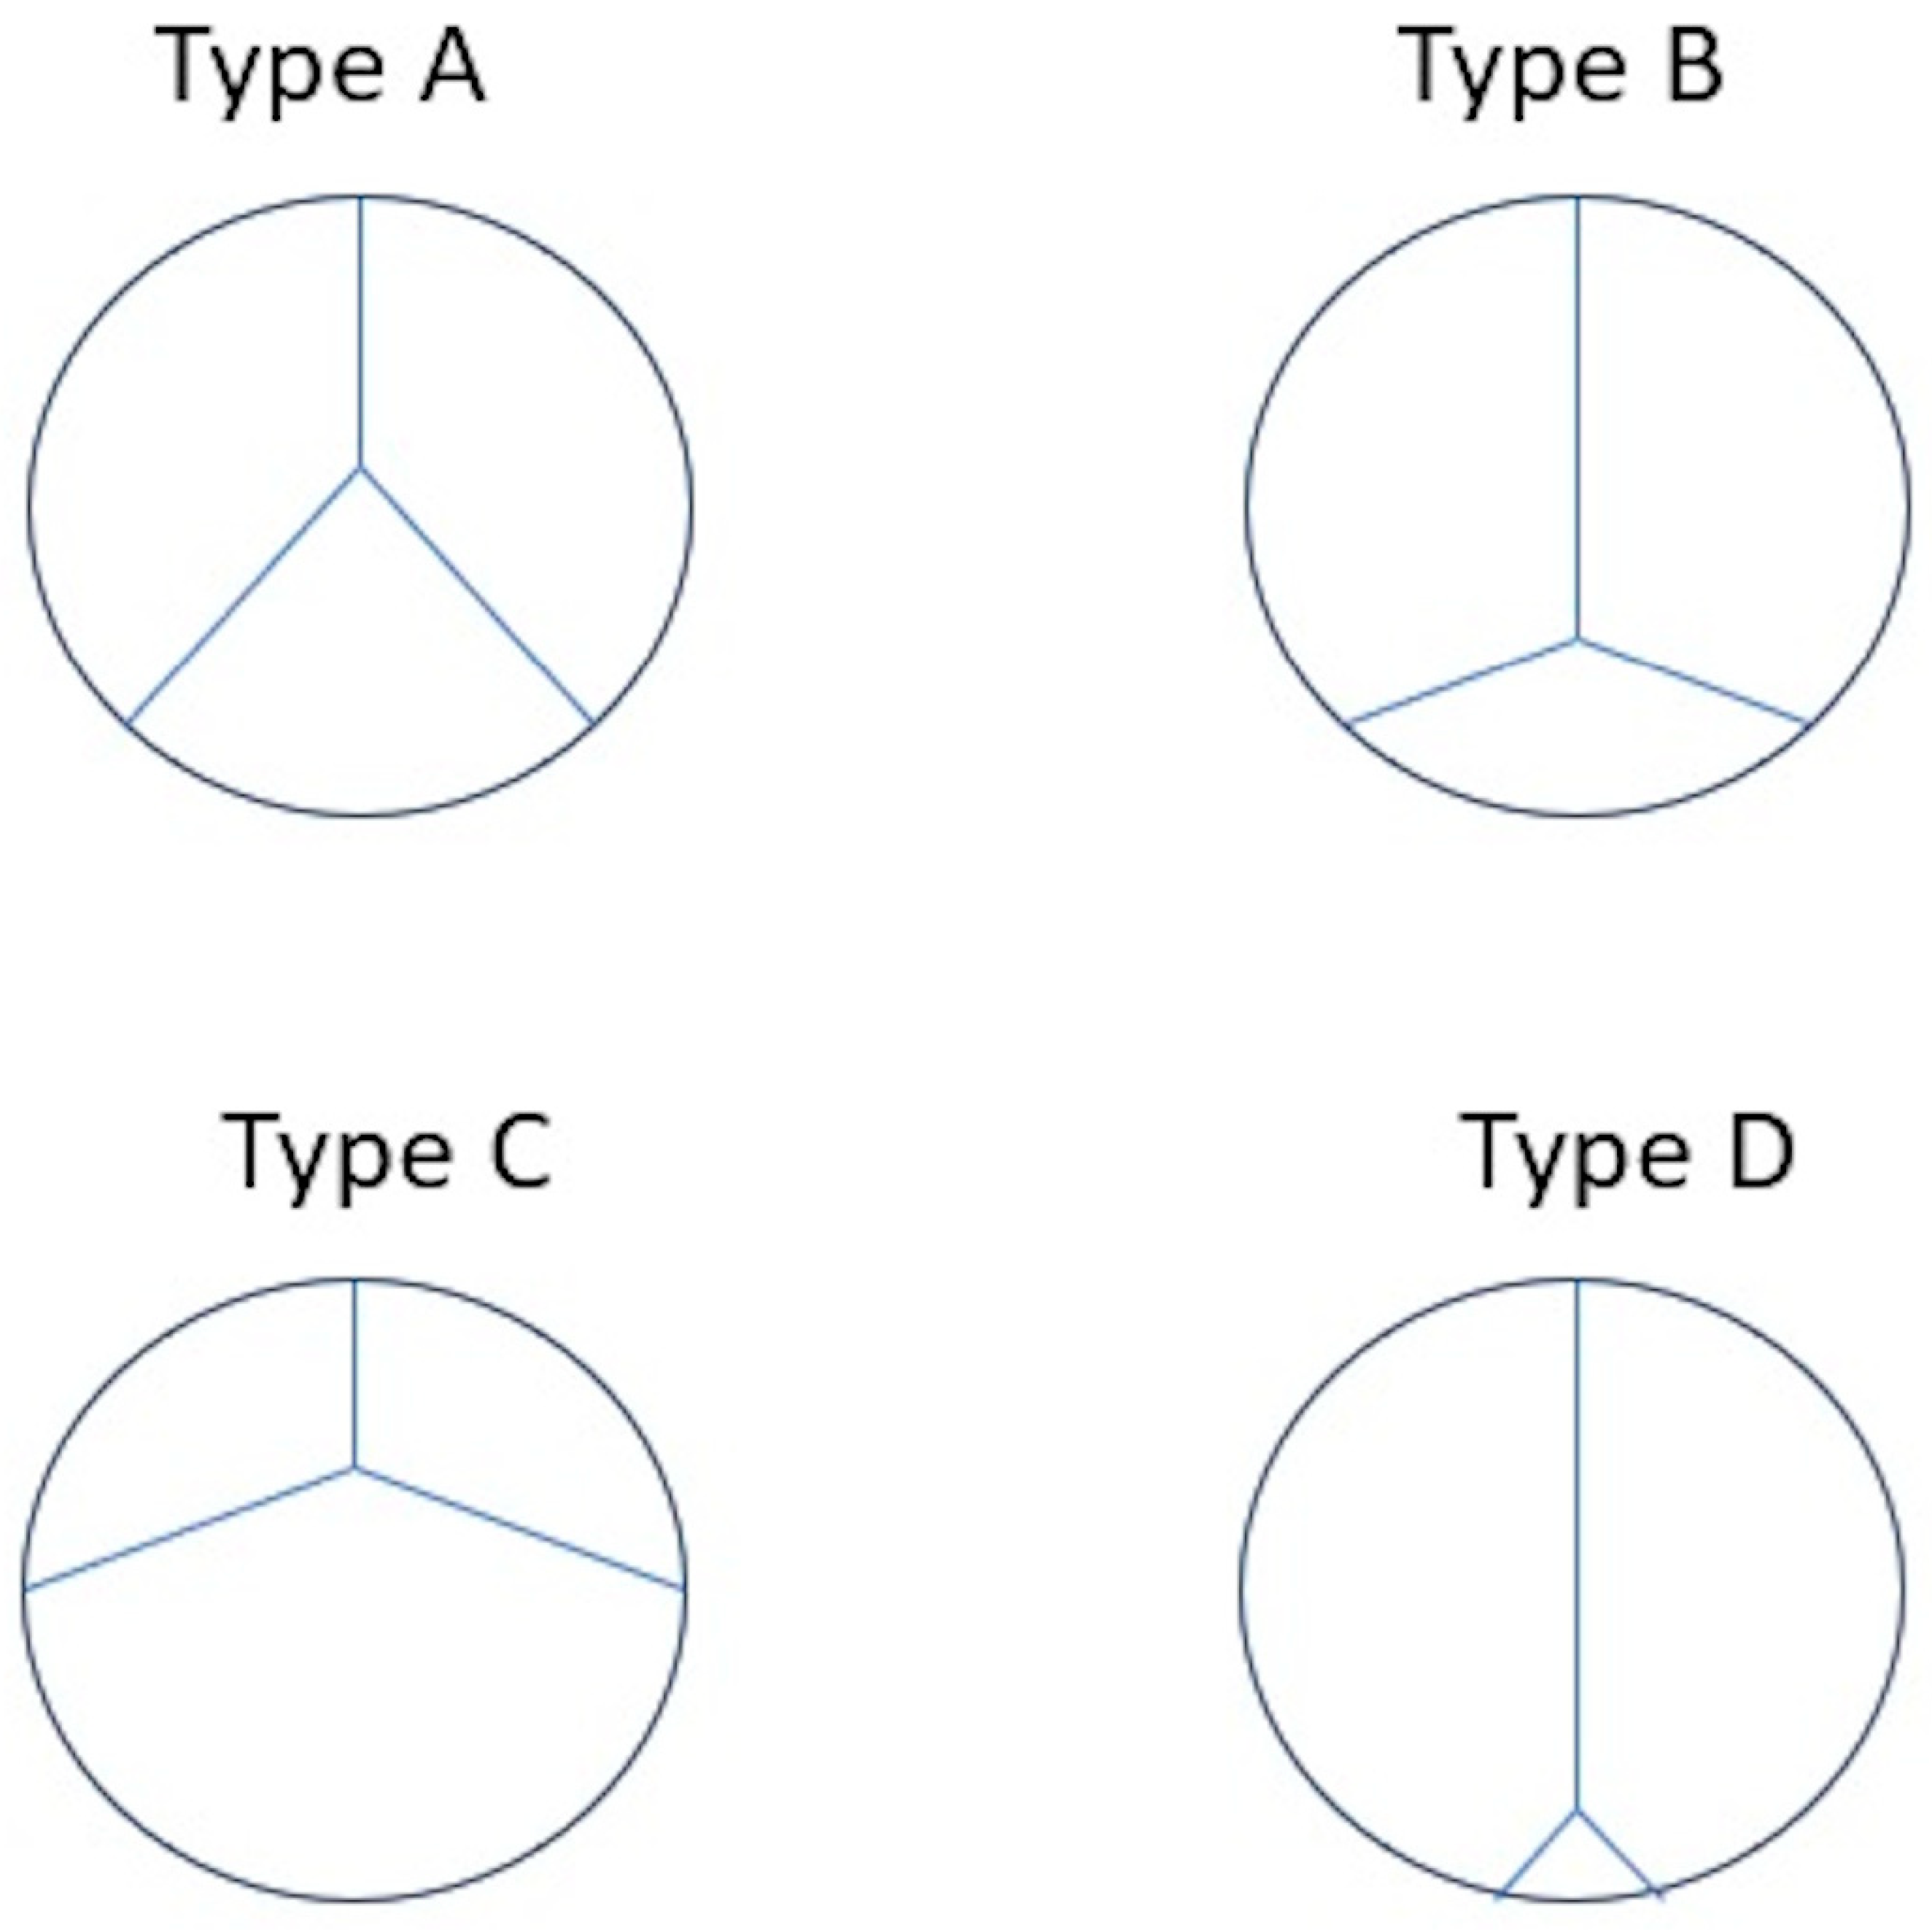

- Boe, B.A.; Cheatham, S.L.; Armstrong, A.K.; Berman, D.P.; Chisolm, J.L.; Cheatham, J.P. Leaflet morphology classification of the Melody Transcatheter Pulmonary Valve. Congenit. Heart Dis. 2019, 14, 297–304. [Google Scholar] [CrossRef] [PubMed]